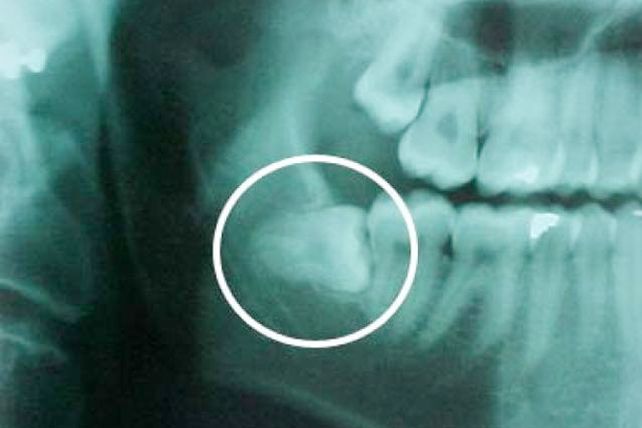

Según los cirujanos orales y maxilofaciales la extracción de estas piezas dentales sólo se deben realizar "cuando puedan existir infecciones de repetición, dolor, quistes o daño potencial al segundo molar".

Por su parte, para el Dr. Fernando García-Marín, del Servicio de Cirugía Oral y Maxilofacial del Hospital Central de la Defensa Gómez Ulla, "hay que extraer la muela cuando ésta asoma en la boca pero está atascada en su erupción y hay riesgo de infección". Y también cuando hay interferencias con prótesis u ortodoncias también se hace necesaria su extracción.

Diversos estudios prueban que el postoperatorio después de una extracción de las muelas del juicio está condicionado por muchos factores. Una investigación publicada en la revista oficial de la Asociación Americana de Cirugía Oral y Maxilofacial en febrero, y realizada por la Universidad de Heidelberg (Alemania) concluye que hay "una correlación significativa entre el nivel de dificultad de la extracción quirúrgica del tercer molar inferior y la tasa de complicaciones inflamatorias, debido a la posición en la que se encuentren estas piezas dentales".